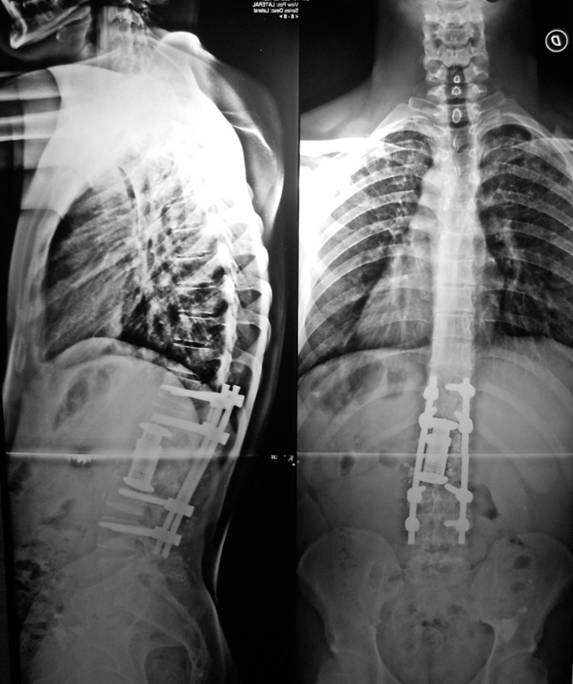

- Figura No 1a

- Figura No 1b

- Figura No 1c

- Figura No 1d

- Figura 1 Texto